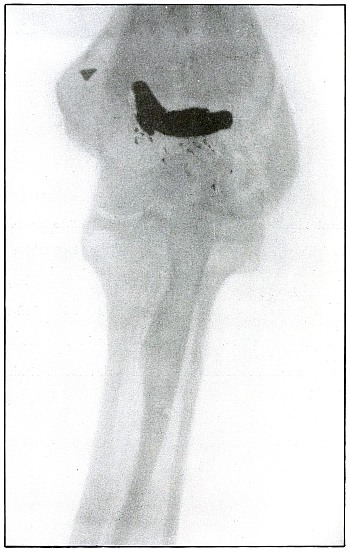

Plate 59.

_

Rifle—Plate 59.

LOWER EXTREMITY.

Gunshot Wound of the Left Knee-Joint,

with Lodgment of the Missile in the Joint.

The course of the bullet was transverse, entering the capsule posterior to the patella without injury to the bone.

As its shadow projection is almost circular, the bullet must be standing almost on its end pointing toward the plate with its long axis almost parallel to the line of projection.

As the fibular side of the leg lay next to the plate and as the only slightly enlarged shadow of the bullet indicates it to be near the plate, its position is in the joint near the fibular side.

As the bullet is undeformed and its penetrating power very slight, its velocity was that of extreme range.

The emergency treatment, is, of course, a simple antiseptic dressing with the leg held in the most comfortable position by muscular action.

The subsequent treatment is removal of the bullet when proper surgical conditions obtain. [Pg 130]